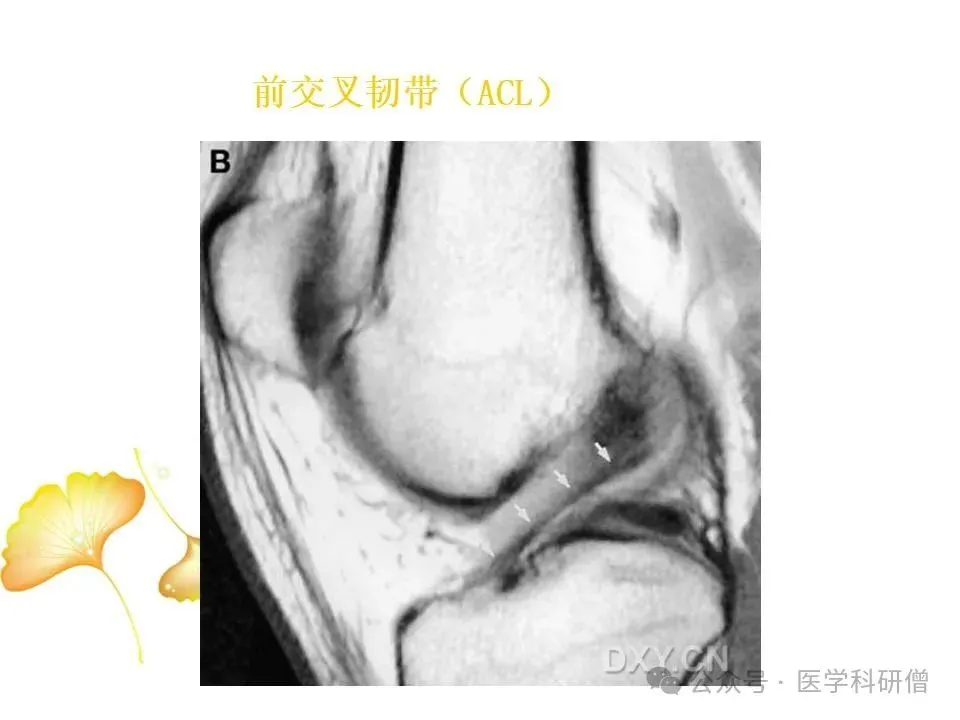

• 前交叉韧带(ACL):位于膝关节内部,负责防止胫骨向前滑动以及控制膝关节的旋转运动。